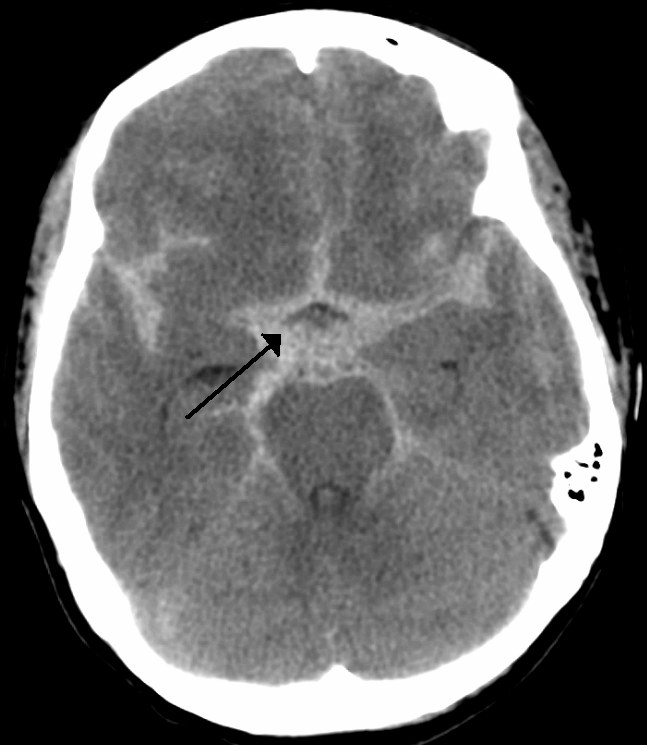

지주막하 출혈은 뇌를 감싸는 막 중 지주막(subarachnoid space) 아래 공간에 갑자기 출혈이 발생하는 질환입니다. 여기서 지주막이란 뇌를 보호하는 세 겹의 막 중 중간층을 가리키며, 이 공간에는 뇌척수액(CSF)이 흐르고 있습니다. 가장 흔한 원인은 뇌동맥류(Cerebral Aneurysm) 파열인데, 뇌동맥류는 뇌혈관 벽이 약해져서 풍선처럼 부풀어 오른 상태를 말합니다.

진단은 응급실에서 뇌 CT 촬영으로 시작합니다. CT상 이상이 보이지 않을 경우 척수액 검사(요추천자)를 통해 출혈 여부를 확인하게 됩니다. 출혈의 원인을 정확히 파악하기 위해서는 뇌혈관 조영술(Cerebral Angiography)을 시행하는데, 이 검사로 동맥류의 위치와 크기를 정확히 확인할 수 있습니다. 최근에는 CT 혈관조영술(CTA)도 많이 활용되고 있습니다.